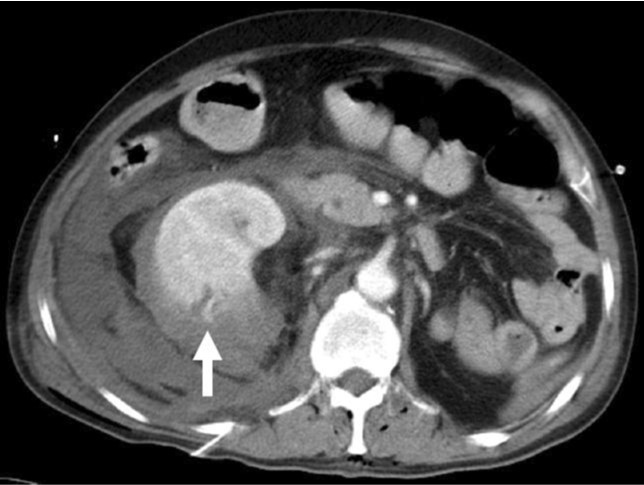

내원 당시 시행한 CT에서 우측 흉곽기종 및 피하기종이 관찰되며 우측 단신장 주위에 출혈을 포함한 특이사항 보이지 않았다(Fig. 1). 입원 12일째 시행한 CT에서 우측 신장 주위로 많은 양의 혈종이 있었으며 중극(midpole) 부위에 현성 출혈로 판단되는 조영제 유출이 보였다(Fig. 2).

Fig. 2.

Fig. 2. Contrast-enhanced CT on 12 days after admission showed a distinctly abnormal leakage of contrast (arrow) within the mid portion of right kidney and a large amount of perirenal hematoma.